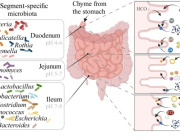

Bacteroides are the most common bacteria species found in the human intestinal tract. Dennis Kunkel Microscopy/Science Source

Previous analyses of gut microflora revealed associations between specific microbes and host health and disease status, genotype and diet.